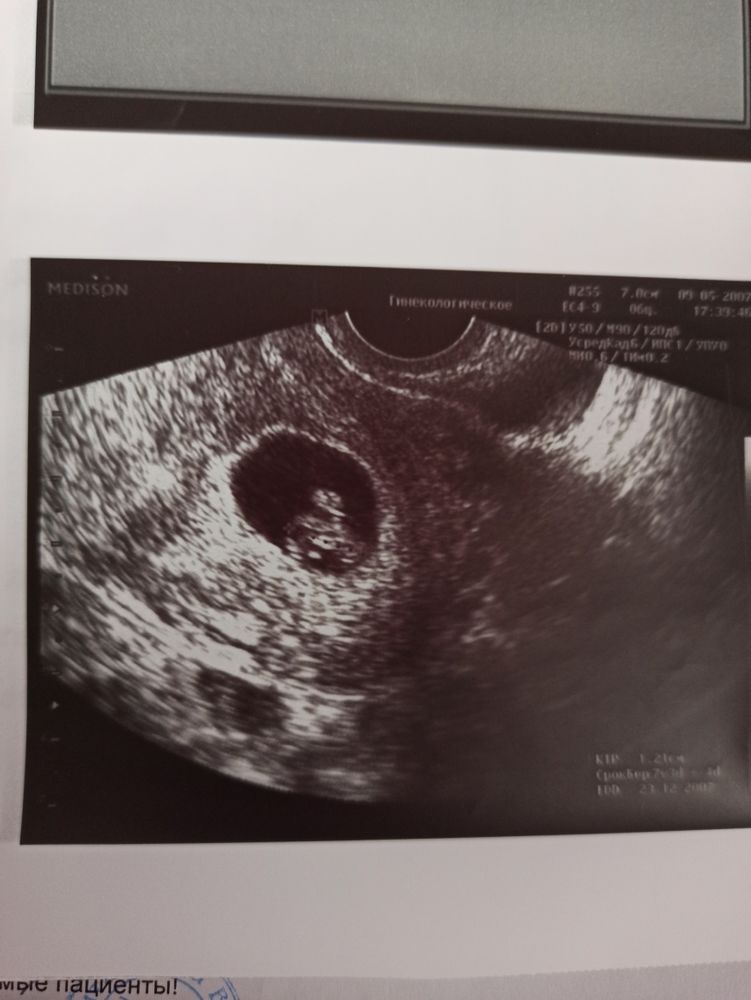

И как я и обещала по методу Рамзи У нас прикрепление слева - девочка